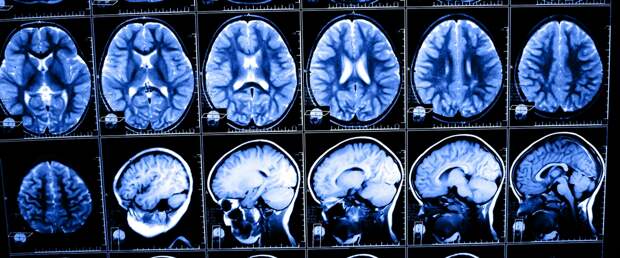

Повышенная активность BACE2 способствовала предотвращению или замедлению развития болезни Альцгеймера в ткани головного мозга, выяснили ученые.

Другим важным достижением стала разработка платформы для быстрого тестирования экспериментальных лекарств для лечения деменции. Сегодня многие клинические исследования ограничены тем, что испытания препаратов проходят уже на стадии, когда у людей развиваются симптомы болезни. И обычно это уже достаточно поздно, чтобы достигнуть значительного терапевтического эффекта.

В основе подхода ученые использовали клетки людей с синдромом Дауна. Они перепрограммировали их в стволовые клетки, а затем превратили в клетки мозга. Это позволило наблюдать за развитием клеток в чашке Петри, чтобы в короткие сроки оценивать влияние препаратов на проявляющиеся патологические изменения.

В частности ученые наблюдали, как два экспериментальных лекарства предотвращали выработку бета-амилоида, которые считаются главными признаками развивающейся нейродегенерации, в клетках головного мозга. Их подход позволит разработать более совершенную модель болезни, чтобы быстро оценивать потенциально эффективные лекарства и продолжать исследования только с наиболее перспективными лекарствами-кандидатами.